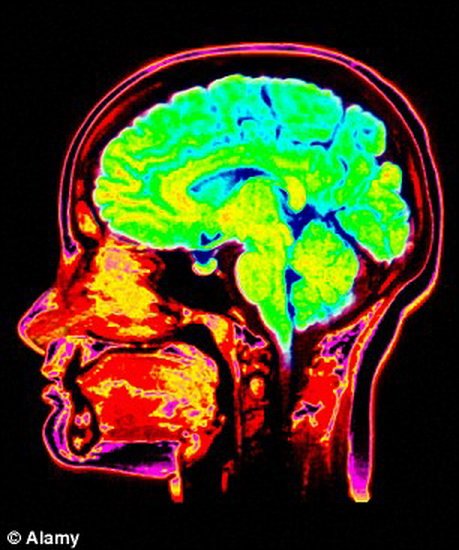

他们表示核磁共振成像呈现出当观看人类故意受到伤害的视频录像时严重精神病患者和普通人的大脑结构反应差异,美国芝加哥大学科学家对18-50岁之间被评估具有精神错觉特征的80位男性囚犯进行了研究分析。大约20-30%的美国囚犯被认为遭受精神病患者影响,相比之下仅有1%的普通人群声称遭受精神病患者的影响。

研究参与者在观看人们有意遭受伤害和面对疼痛的视频时进行了大脑扫描成像,该研究揭晓了为什么像《沉默的羔羊》中变态杀手汉尼拔缺乏同情怜悯之心。精神病患者在大脑重要区域具有较低的活跃性,其中包括:杏仁核,一种杏仁状神经束,对于处理恐惧、生气和快乐等情感具有重要作用。

研究人员指出,大脑杏仁体和额叶皮层的观测结果与之前对精神病患者的研究分析相一致。相反的是,在精神病患者大脑终脑皮层和脑岛区域具有更强的活跃性,脑岛区域的较高活跃性记录令科学家们感到吃惊,它对于影响人类情绪极为重要。目前,这项研究报告发表在日前出版的《美国医学会杂志——精神病学》上。